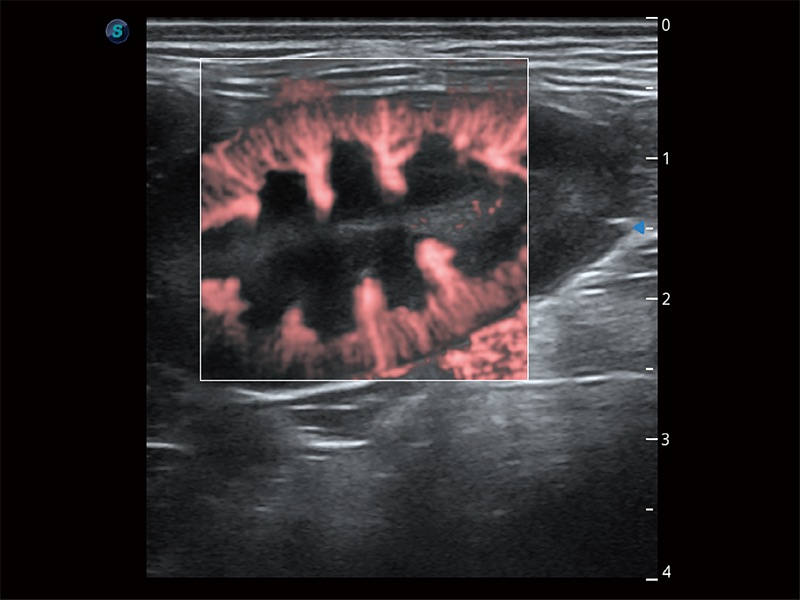

• Micro F 显微血流成像

极大提升超低速微细血流的检出能力,同时更精准地滤除软组织和超声信号,为兽用医生提供以往无法通过常规血流获得的疾病诊断信息。

• Bright Flow 立体血流成像

在传统二维血流成像的基础上,呈现血流的立体感,具有动感的生命力之美。即便是微小的血管也能轻松应对,提高了血流的视觉敏感性。